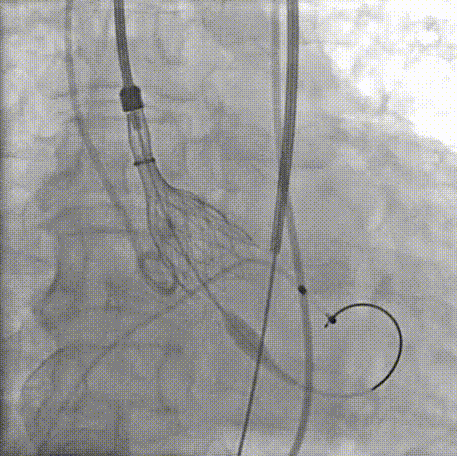

主动脉根部造影轻中度反流

20mm球囊预扩,有腰无漏,冠脉显影良好

TaurusOne轻松过弓

瓣膜定位

瓣膜释放

金牛瓣精准“开花”

瓣膜瓣叶正常工作